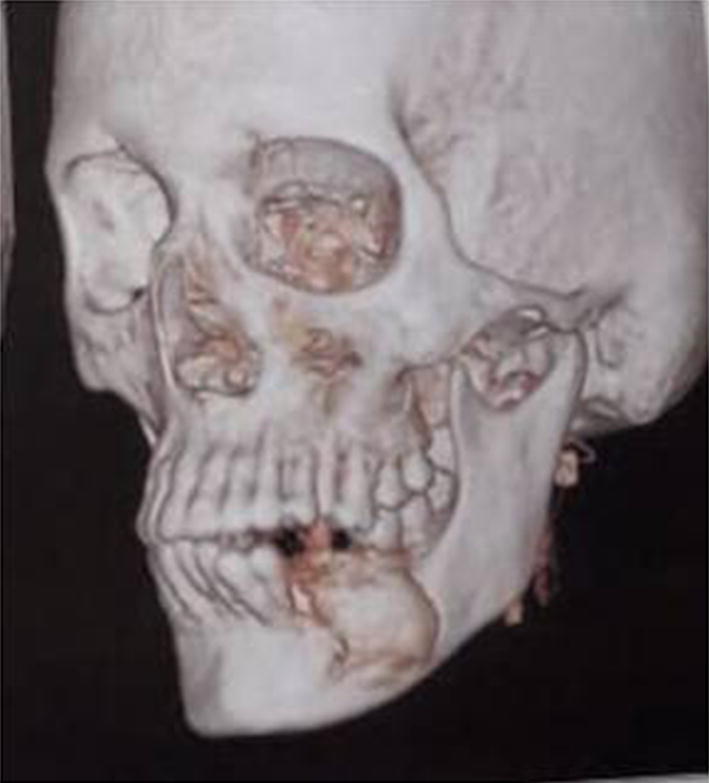

An orthopantomogram (OPG) showed radiopaque mass measuring about 3x3 cm in left body of mandible showing classical sun burst appearance (Fig. 2). 3D MDCT scan showed large bony mass lesion involving left body of the mandible measuring 41.8 mm × 25.4 mm with osteoid bone matrix and adjacent periosteal reaction (Fig. 3). Axial view CT scan confirmed the clinical finding of lingual cortical expansion (Fig. 4). Clinical and radiographic features were strongly suggestive of osteosarcoma of body of mandible. Routine haematological investigations were done. An open biopsy was performed with direct incision over the bone in the representative region; adequate size of bone tissue was removed using straight hand piece and copious saline irrigation. Continuous oozing was observed from the lesion obscuring the field. Incisional biopsy was also obtained from overlying soft tissues. Haemostasis was achieved by using local haemostatic measures. Samples were sent for histopathological examination which on H and E stained section showed osteoid material with atypical osteocytes, at focal areas chondroblastic tissues with atypical cells were evident while few sections showed cellular areas blending into malignant osteoid tissues confirming the diagnosis of OS of body of mandible (Fig. 5). The soft tissue biopsy was inconclusive. Patient was then referred to oncology department for further management. There she underwent hemi-mandibulectomy with disarticulation followed by free fibula microvascular reconstruction and followed by adjuvant chemotherapy. Final diagnosis of osteosarcoma of body of mandible with a skip metastastatic lesion in mandibular condyle was confirmed from histopathology reports.

Fig. 3.

3D CT showing extent of lesion over body of mandible and periosteal reaction

Radiological feature is of utmost importance as it acts as guide for the pathologist to correlate with clinic-pathological findings. Radiographic attributes include widening of periodontal ligament space along with the enfeeblement of lamina dura around a jaw tumour [6, 7]. However our patient had previous history of extraction of tooth in the same region, so the latter finding was truant. Radiographic appearance is based on the histological changes present in particular stage of osteosarcoma. It may display either bone formation (osteogenic), bone destruction (osteolytic) or a combination of both. Our patient’s OPG showed diffuse radiopacity in left body of mandible similar to that of classic “sun burst” appearance of osteosarcoma indicating malignant changes in the process of osteoid formation. Though OPG acts as a chaperon in the differential diagnosis, it has its own pitfalls such as image distortion and magnification. CT scan or MRI scan can be used as an advanced diagnostic tool to conclude on a more definitive diagnosis. The CT scan of our patient clearly delineated periosteal reaction with bony expansile lesion and osteoid bone matrix showing strong proclivity towards OS.